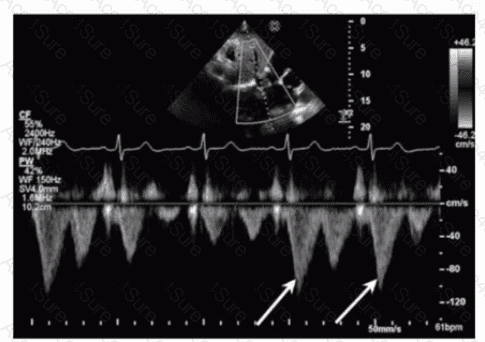

Which flow component is indicated by the arrows on this image?

The Doppler waveform shows pulmonary vein flow with several components. The arrows point to small reversed flow spikes just after the atrial contraction wave, which corresponds to the atrial reversal (AR) flow component. Atrial reversal occurs as blood briefly flows backward into the pulmonary veins during atrial contraction.

Ventricular reversal is not typically seen in pulmonary veins. Diastolic flow reversal is abnormal and usually not part of normal pulmonary vein flow. Systolic forward flow is the major forward component during ventricular systole.

This interpretation is standard in ASE guidelines on diastolic function assessment and pulmonary vein Doppler evaluation【12:ASE Diastolic Function Guidelines†p.85-90】【16:Textbook of Clinical Echocardiography, 6e†p.130-135】.